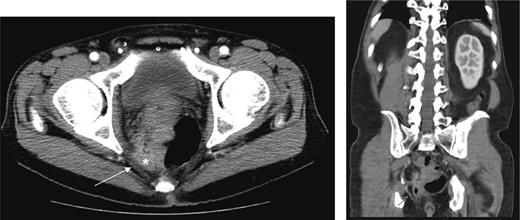

Contrast-enhanced computed tomography (CT) scan revealed the presence of diverticulosis and perirectal mesenteric stranding concerning for diverticulitis (Fig. 1); therefore, the patient was admitted and treated empirically for the same with i.v. antibiotics. He was discharged several days later with a 2-week course of amoxicillin clavulanate.

CT scan depicting perirectal stranding without definite abscess formation.